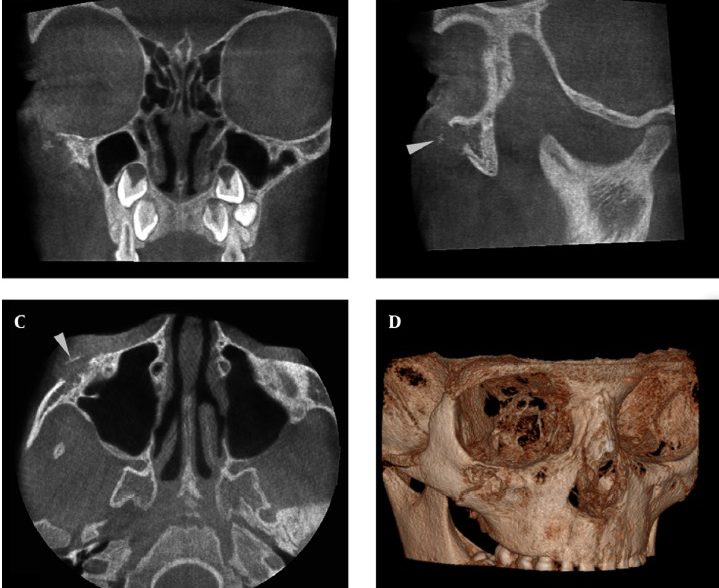

Desmoplastic Fibroma, Report of a Rare Case in Infraorbital Rim